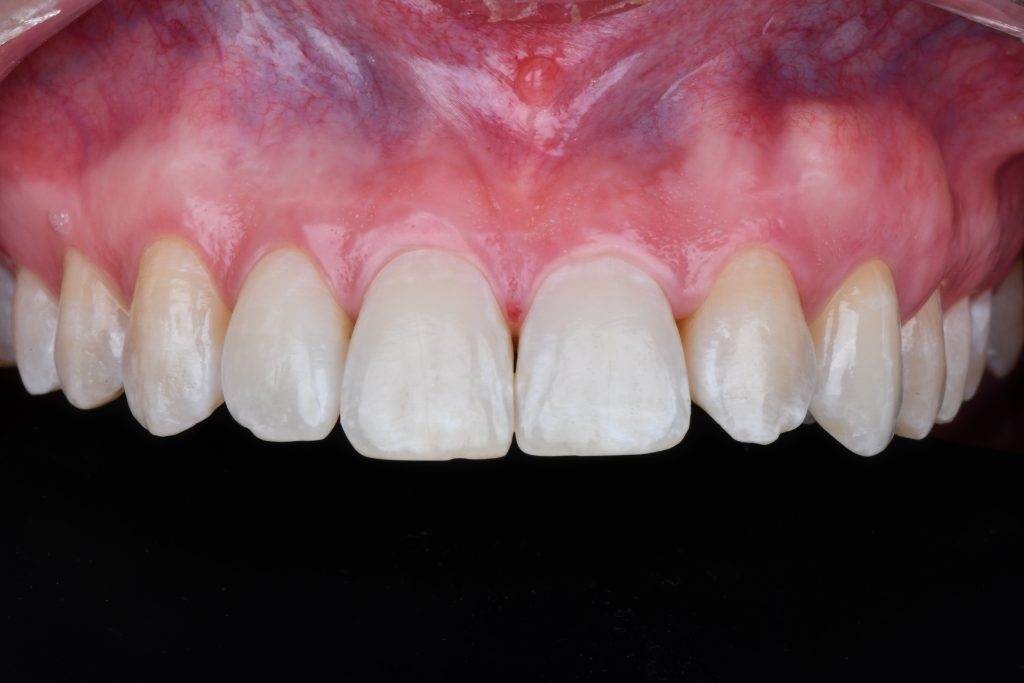

A 24-year-old female patient referred by an orthodontist who resolved the unilateral agenesis of the left upper lateral incisor by mesializing the left upper cuspid and shifting the gap in between teeth 23 and 25. After confirming the free bone corridor between the roots of the cuspid and the first bicuspid, a Straumann BLX RB implant (3.75 mm) was inserted and thin soft tissue buccally augmented with tuberosity connective graft. A sliding island flap on the palatal side relieved tension while suturing both sides of the mucosa. Three months later, the ortho appliance was removed and a temporary crown (Cerasmart) was delivered. All teeth were whitened and after four-month-period, an all-ceramic crown (Katana) was made and fixed. The patient denied and reshaping of the tooth 23. In 3 years, the situation is sthbilized however the prognosis of the tissue covering the tooth 23 is doubtful. Prosthetic part of the treatment done by a.krugova

the tooth 23 is already in contact with the upper left incisor

the root of the tooth 23 was moved out of the bone envelope however the patient denied to continue in ortho Tx

the tooth 23 still in shape of a cuspid